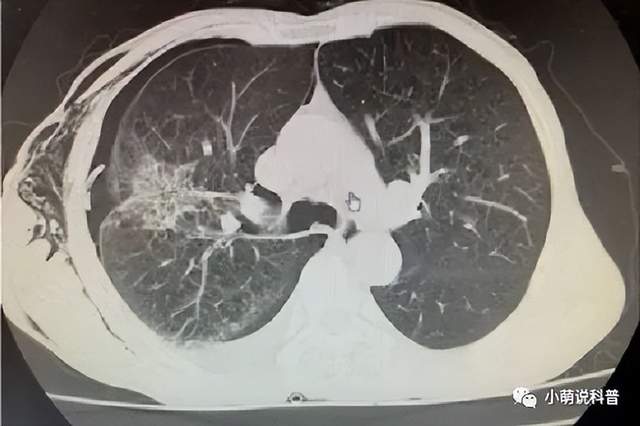

患者经CT引导在局麻下行右肺癌经皮微波消融术,手术仅用了8分钟就顺利完成,术中患者仅感局部轻微疼痛,余无特殊不适症状,术后患者感觉良好,复查CT肿瘤消融满意,仅少量气胸。

消融治疗中

治疗后肺肿瘤消散